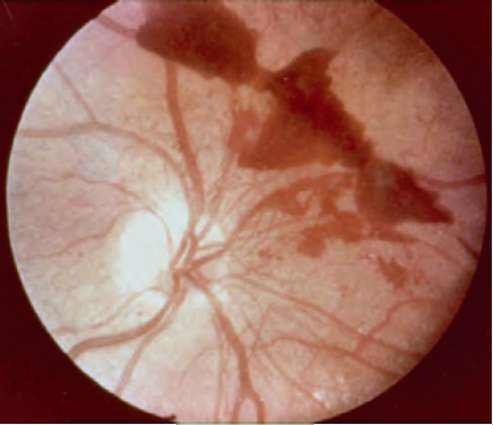

Рис. 20.6. Кровоизлияние на глазное дно при гипертонической ангиопатии сетчатки